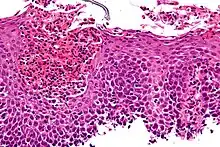

Microscopic Slide of Infectious Esophagitis

Infectious esophagitis

Esophagitis happens due to a viral, fungal, parasitic or bacterial infection. More likely to happen to people who have an immunodeficiency. Types include:

Microscopic Slide of Eosinophilic Esophagitis

Eosinophilic esophagitis

Eosinophilic esophagitis is caused by a high concentration of eosinophils in the esophagus. The presence of eosinophils in the esophagus may be due to an allergen and is often correlated with GERD. The direction of cause and effect between inflammation and acid reflux is poorly established, with recent studies (in 2016) hinting that reflux does not cause inflammation.[6] This esophagitis can be triggered by allergies to food or to inhaled allergens. This type is still poorly understood.